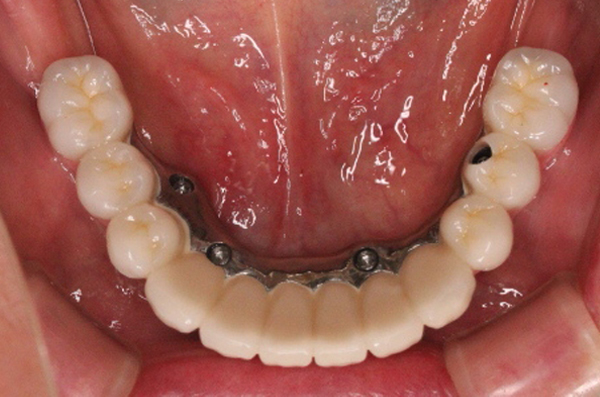

オールオン4

下顎すべてが欠損の為、4本埋入し、入れ歯ではなくインプラントブリッジ(オールオン4)にて改善。

手術 150万円 上部構造 60万円(税別)

- 喫煙者の方は、インプラント周囲炎やインプラント脱離のリスクが高まります。

- 当院ではナイトガードを使用していただいています。

- 骨幅が足りない、神経までの距離が短いケースは手術を行えないこともあります。